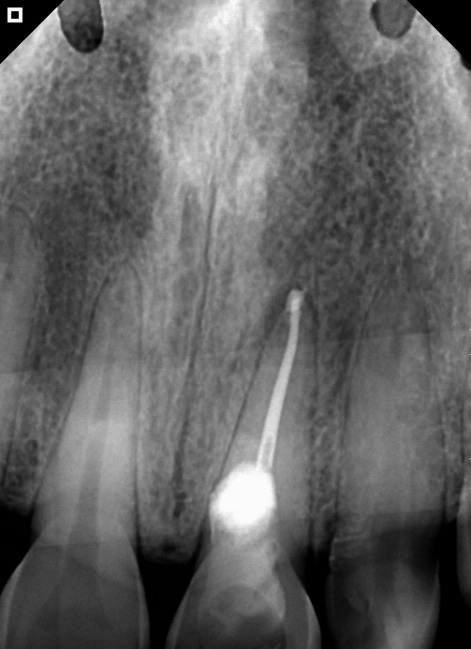

In the second session, absolute isolation was achieved using a rubber dam. The area was irrigated with 2.5% sodium hypochlorite. The canal was located, instrumented, and filled with gutta-percha and Bio-C Sealer bioceramic cement (Angelus) (Figure 3A). The treatment was performed with the aid of an operating microscope to obtain magnification (Figure 3B).

Figure 3: Radiograph after completion of root canal filling (B)